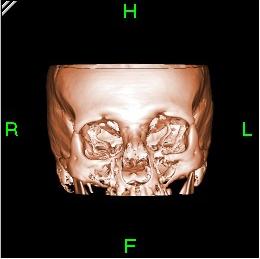

CT produces a volume of data that can be manipulated, through a process known as windowing, to identify various structures based on their ability to block the X-ray (Röntgen) beam. Although historically the images generated were in the axial or transverse plane (orthogonal to the long axis of the body), modern scanners allow this body of data to be reformatted in various planes or even as volumetric (3D) representations of structures.

Three-dimensional (3D) image reconstruction

The principle

Because contemporary CT scanners offer isotropic, or near isotropic, resolution, display of images does not need to be restricted to the conventional axial images. Instead, it is possible for a software program to build a volume by 'stacking' the individual slices one on top of the other. The program may then display the volume in an alternative manner.

Multiplanar reconstruction

3D rendering techniques

- Surface rendering

- A threshold value of radiodensity is chosen by the operator (e.g. a level that corresponds to bone). A threshold level is set, using edge detection image processing algorithms. From this, a 3-dimensional model can be constructed and displayed on screen. Multiple models can be constructed from various different thresholds, allowing different colors to represent each anatomical component such as bone, muscle, and cartilage. However, the interior structure of each element is not visible in this mode of operation.

- Volume rendering

- Surface rendering is limited in that it will only display surfaces which meet a threshold density, and will only display the surface that is closest to the imaginary viewer. In volume rendering, transparency and colors are used to allow a better representation of the volume to be shown in a single image—e.g. the bones of the pelvis could be displayed as semi-transparent, so that even at an oblique angle, one part of the image does not conceal another.

Example

Some slices of a cranial CT scan are shown below. The bones are whiter than the surrounding area. (Whiter means higher radiodensity.) Note the blood vessels (arrowed) showing brightly due to the injection of an iodine-based contrast agent.

A volume rendering of this volume clearly shows the high density bones.

After using a segmentation tool to remove the bone, the previously concealed vessels can now be demonstrated.